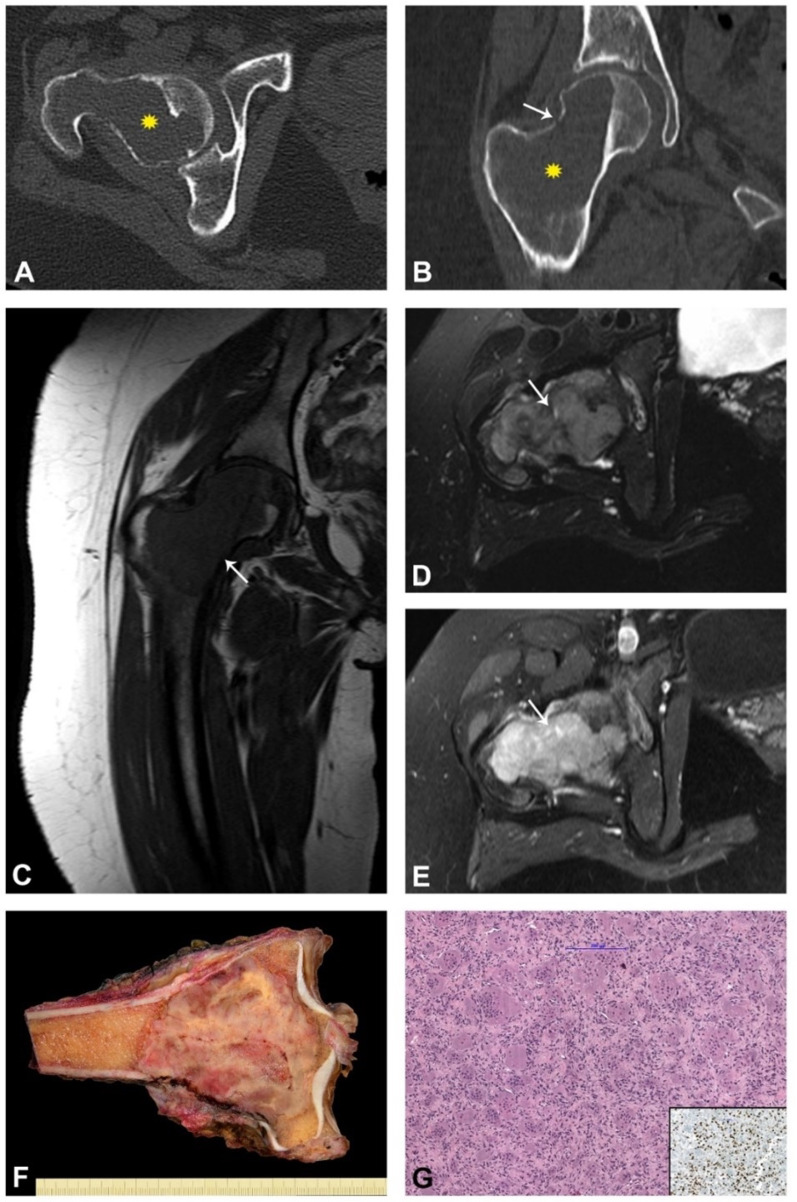

背景:骨巨细胞瘤(GCTB)的诊断和治疗方式的进步引入了分子和放射学工具来改进临床决策。H3.3 G34W免疫组化染色已成为常规诊断标志物,而H3F3A突变分析增强了对预后的认识。治疗主要包括手术方法,如刮除或整体切除,在高风险或不能手术的病例中,denosumab作为辅助。方法:回顾性分析55例GCTB患者的临床病理和影像学表现。采用Campanacci分级系统对肿瘤进行评估。采用H3.3 G34W抗体免疫组化分析和下一代测序(NGS)检测H3F3A突变。对接受denosumab治疗的9例患者的亚组进行进一步的临床结果和组织学变化分析。结果:该队列的平均年龄为37.7岁,肿瘤最常影响膝关节(55%)。所有检测的肿瘤均显示H3.3 G34W阳性染色,其中8个肿瘤显示H3F3A G34W突变。刮除术后复发率为32%,整体切除后复发率为18%。Denosumab治疗平均14.6个月,促进肿瘤缩小和新骨形成,无主要副作用。组织学上,治疗后的肿瘤显示巨细胞耗竭和骨基质沉积增加。结论:手术仍然是GCTB治疗的基石,根据肿瘤特征进行刮除或切除。Denosumab在高风险病例中提供了有价值的辅助手段,提高了手术的可行性并促进了关节的保护。Campanacci分级系统仍然是预测和治疗计划的重要工具,特别是在分子和放射诊断的补充下。未来的研究应侧重于将先进成像技术与人工智能技术相结合,实现GCTB的个性化管理。证据等级:四级。

Results: The cohort had a mean age of 37.7 years, with tumors most commonly affecting the knee joint (55%). All tested tumors demonstrated positive H3.3 G34W staining, with eight exhibiting H3F3A G34W mutations. Recurrence rates were 32% following curettage and 18% after en bloc resection. Denosumab treatment, administered for an average of 14.6 months, facilitated tumor downsizing and new bone formation without major side effects. Histologically, treated tumors showed a depletion of giant cells and increased bone matrix deposition.